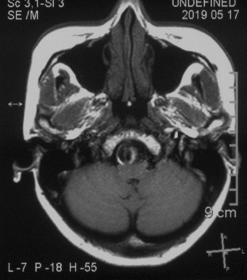

2019.5.17外院头颅MR

患者核磁共振显示脑桥-延髓前方流空影,考虑动脉瘤,有明显的双腔征,瘤壁有加强,且对脑干有一定的压迫。